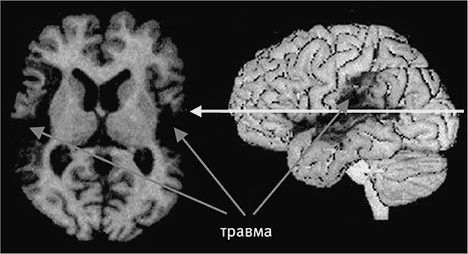

Рис. п.1.Общий вид и срез головного мозга человека

Человеческий мозг, вид сбоку (вверху). Стрелкой отмечено место, где прошел срез, показанный на нижней фотографии. Наружный слой мозга (кора) состоит из серого вещества и образует множество складок, позволяющих уместить большу́ю площадь поверхности в малом объеме. Кора содержит порядка 10 миллиардов нервных клеток.